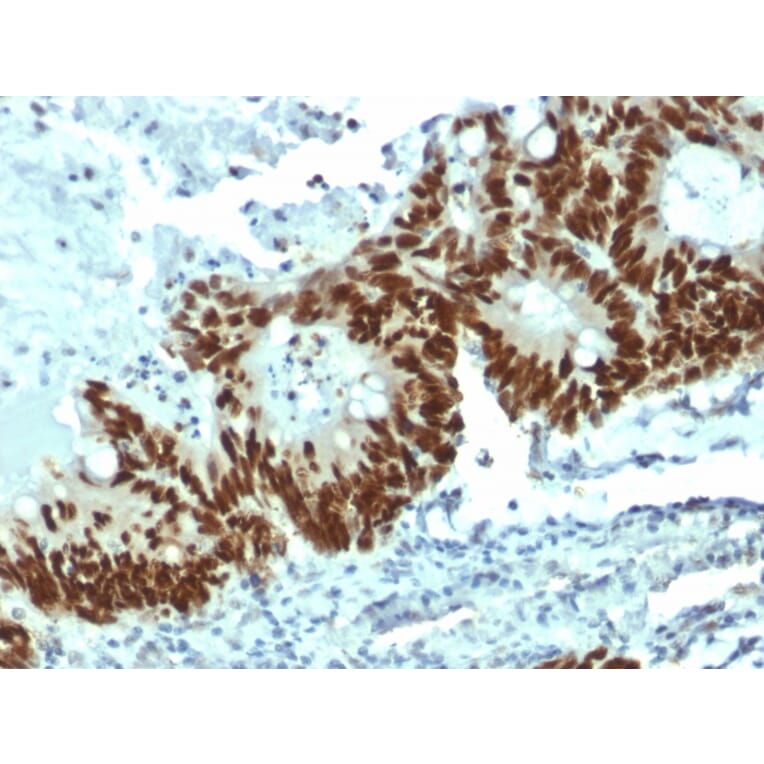

Specificity

This antibody recognizes a 53kDa protein, which is identified as p53 suppressor gene product. It reacts with the mutant as well as the wild form of p53. Its epitope maps within the N-terminus (aa 20-25) of p53. Monoclonal antibody PAb1801 does not block the binding of DO-7 MAb to p53 in an ELISA test. p53 is a tumor suppressor gene expressed in a wide variety of tissue types and is involved in regulating cell growth, replication, and apoptosis. It binds to MDM2, SV40 T antigen and human papilloma virus E6 protein. Positive nuclear staining with p53 antibody has been reported to be a negative prognostic factor in breast carcinoma, lung carcinoma, colorectal, and urothelial carcinoma. Anti-p53 positivity has also been used to differentiate uterine serous carcinoma from endometrioid carcinoma as well as to detect intratubular germ cell neoplasia. Mutations involving p53 are found in a wide variety of malignant tumors, including breast, ovarian, bladder, colon, lung, and melanoma.

Flow Cytometry, IF, WB, IHC-P

Flow Cytometry: 1-2 µg/million cells, IF: 1-2 µg/ml, WB: 1-2 µg/ml, IHC-P: 0.25-0.5 µg/ml